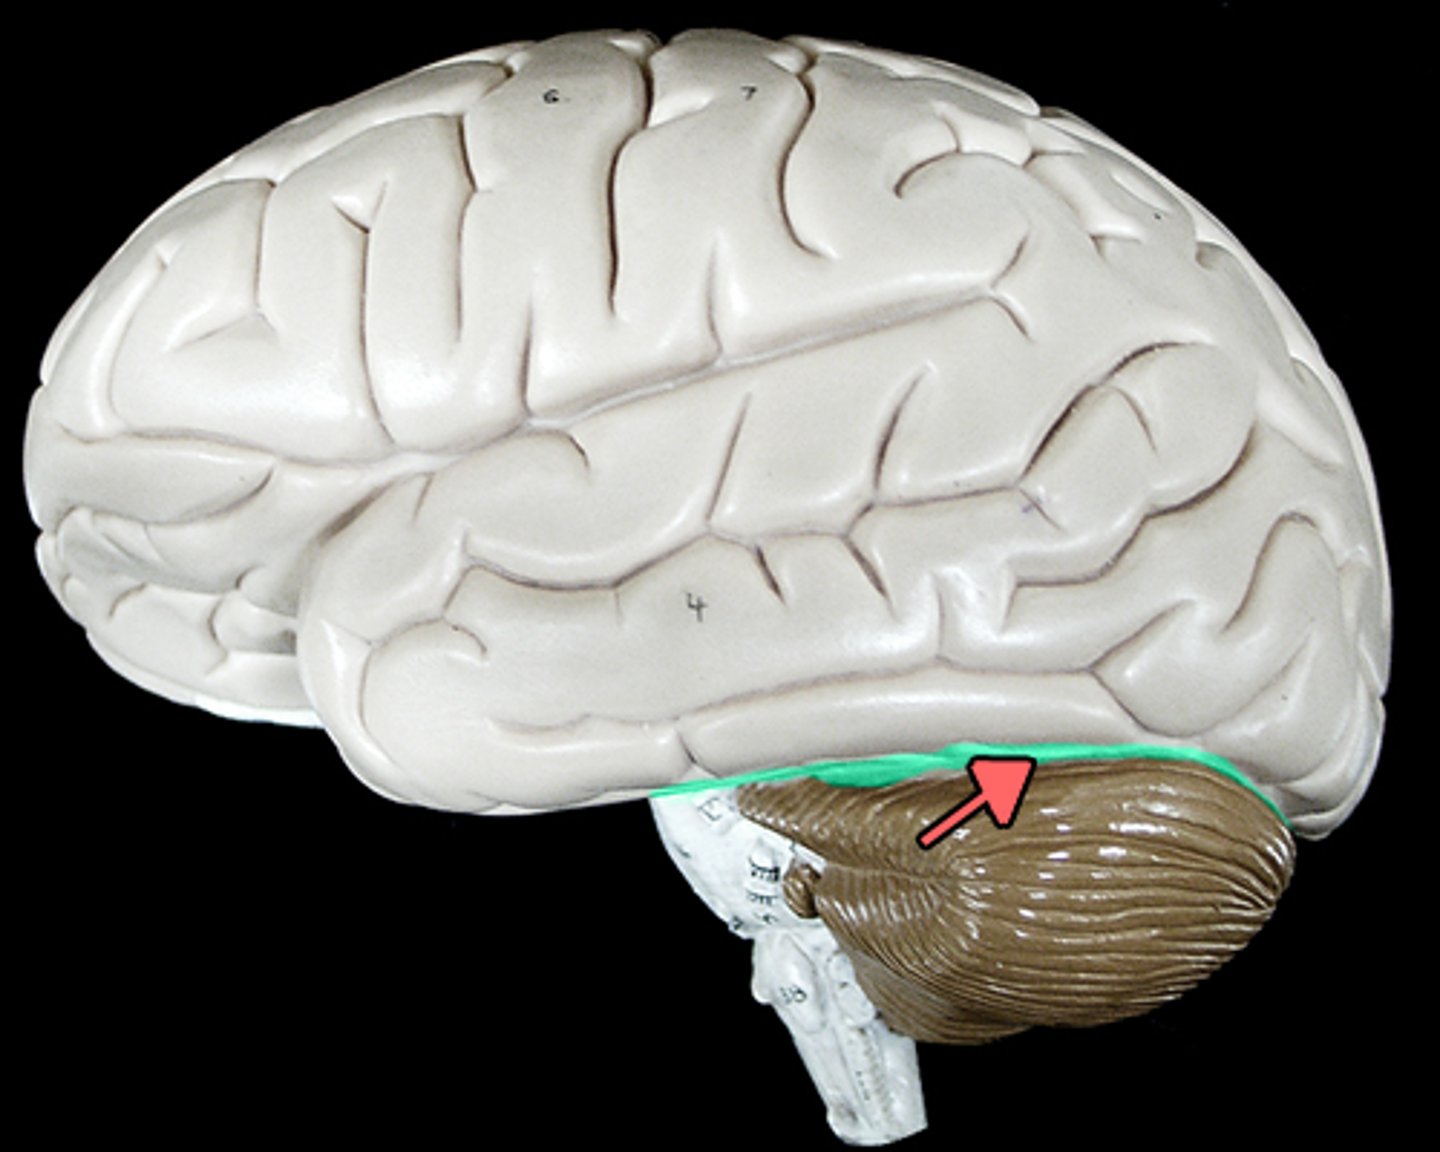

transverse fissure

separates cerebrum from cerebellum